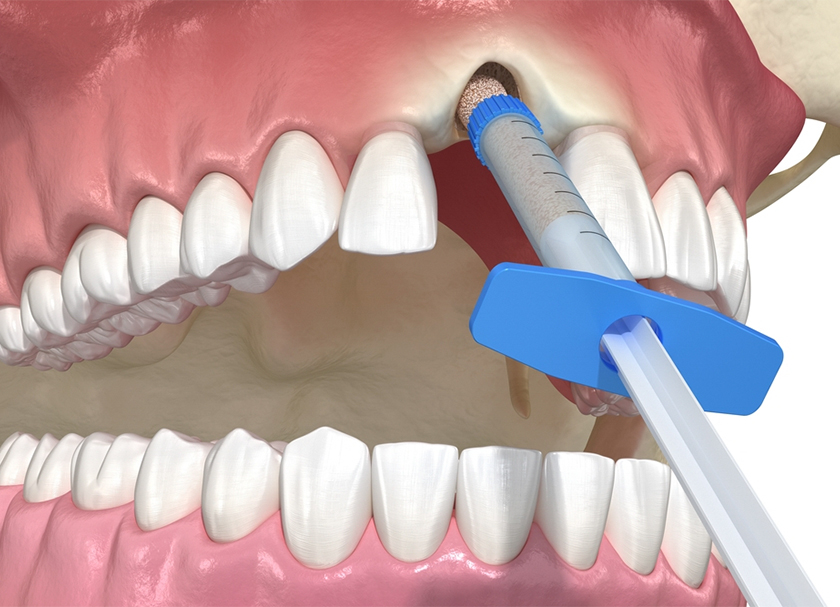

Socket Graft

This socket graft is the most typical bone graft method, which includes adding new bone directly into the cavity left by the extracted tooth to establish a sturdy foundation for the dental implant.

The Process Of Bone Grafting

Anesthesia is given before the procedure to minimize pain. The dentist first cleans the area before making an incision in the gum tissue to reveal the region that needs the bone transplant. The dentist will next use a specific bone grafting substance or a portion of bone taken from another part of your body to add the necessary bone where it is needed on your jaw bone.